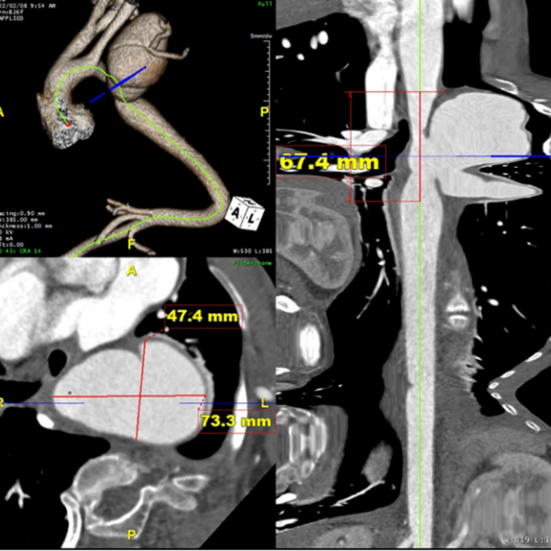

入院后完善进一步检查后发现患者主动脉病变复杂程度远远超过预期。术前检查显示患者左锁骨下动脉瘤最大直径达73.3mm,伴局限性夹层形成,目前瘤体已压迫喉返神经出现声音嘶哑症状,远期发生破裂猝死风险极高。同时,左锁骨下动脉开口近端合并主动脉缩窄,最狭窄处直径仅约10mm。更加雪上加霜的是该患者左椎动脉刚好单独起自主动脉弓狭窄处,且为左椎优势(图1)。结合患者脊柱侧弯畸形病史,进一步查体发现患者存在外耳道、四肢关节等多处畸形,完善基因检测后考虑诊断为Larsen综合征。鉴于患者病史、解剖和主动脉病变的复杂性,开放手术无法充分显露左锁骨下动脉瘤体,更加无法切除瘤体并重建左锁骨下动脉,且开放手术创伤和风险极大。而由于患者主动脉走行扭曲,介入手术存在支架无法输送至目标位置而失败的风险,且腔内重建椎动脉困难,一旦发生内漏,所有努力都将付诸东流。

图1 术前CTA